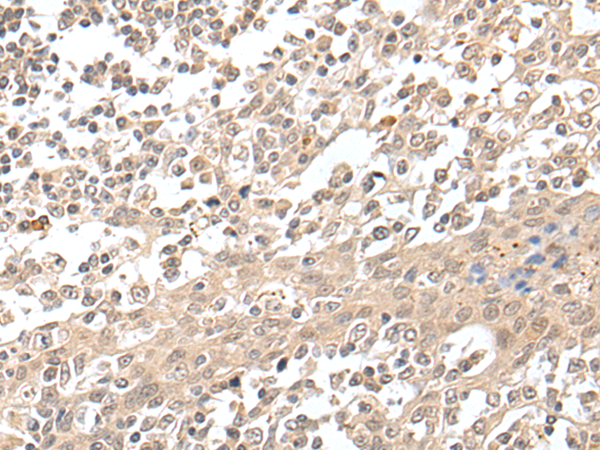

IHC positive control:

Human colorectal cancer and human tonsil

IHC Recommend dilution:

25-100